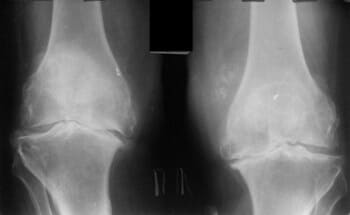

দুই বছর আগে আমি প্রথম আমার হাঁটু এবং নিতম্বে হালকা ব্যথা অনুভব করেছি। ব্যথা তীব্র ছিল না, তাই আমি এটিতে খুব বেশি মনোযোগ দিইনি... দেখা যাচ্ছে যে জয়েন্টের রোগগুলি খুব বিপজ্জনক এবং অবিলম্বে চিকিত্সা করা উচিত, আমার মতো অপেক্ষা করা উচিত নয়। একদিন আমার হাঁটুতে হালকা কিন্তু তীক্ষ্ণ ব্যথা হয়েছিল, এবং আমার নিতম্বের জয়েন্টটি গুরুতরভাবে আঘাত করতে শুরু করেছিল, এবং আমি ভেবেছিলাম যে কিছুই ভুল ছিল না, এটি চলে যাবে, যেমন এটি সাধারণত হয়। আমি ওষুধ ও মলম কিনে ব্যবহার শুরু করলাম। এক সপ্তাহ বা তার পরে, আমার অবস্থা তীব্রভাবে খারাপ হয়ে যায়, ব্যথা অসহ্য হয়ে ওঠে, আমার নিতম্বের জয়েন্টে তীব্র ব্যথা শুরু হয় এবং আমি প্রথমবারের মতো ডাক্তারের কাছে যাওয়ার সিদ্ধান্ত নিয়েছিলাম। তারা আমাকে একটি রোগ নির্ণয় দিয়েছে যা সস্তা ছিল না এবং আমার ডাক্তার পরীক্ষার ফলাফল দেখে আমাকে বলেছিলেন:

"আপনি আগে উপসর্গ উপেক্ষা কেন? আপনার অস্টিওআর্থারাইটিস আছে! অস্টিওআর্থারাইটিস, আপনি যদি অক্ষম হতে না চান তবে আপনাকে নিতম্ব এবং হাঁটু অস্ত্রোপচার করতে হবে!